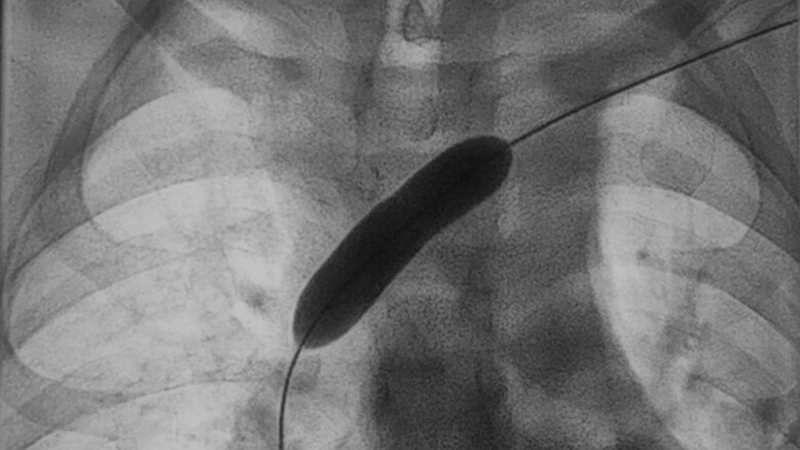

Bei Thrombosen zum Beispiel bietet die Interventionelle Radiologie die Möglichkeit an, mit minimalinvasiven Techniken die Thromben zu entfernen. „Wir öffnen Gefäße wieder, die durch den chronischen Verschluss durch Thrombosen erkrankt sind, und können dort zum Beispiel Stents einbringen, um einen Wiederabstrom zu erreichen“, erläutert Prof. Vogl. „Den Zugang erreichen wir überwiegend über die Blutgefäße, also Arterien beziehungsweise Venen, mit Kathetertechnik.“